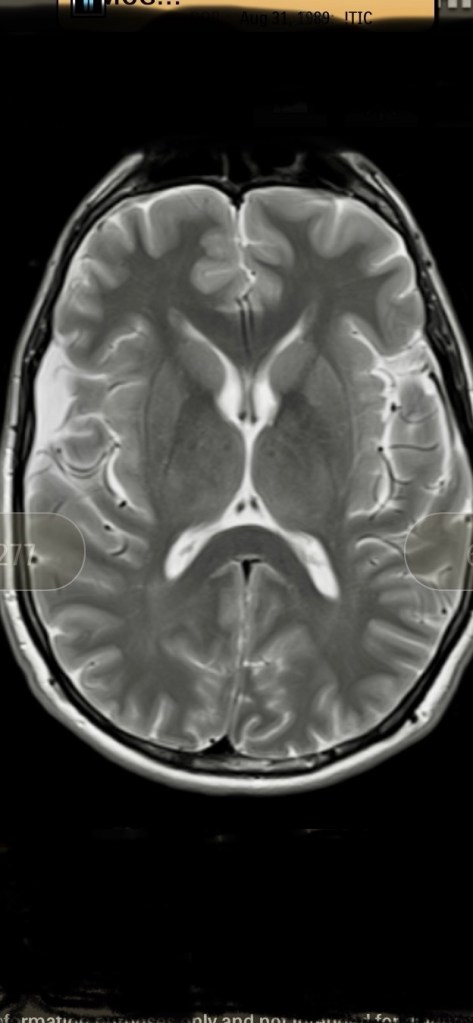

Before I end this blog post, I am going to share with you all one final picture, which is an MRI.

This is an MRI of my brain. Somewhere in the bottom, a neurologist could show you where I have a benign arachnoid cyst. You can search on Google for what an arachnoid cyst is if you’re interested.

If my brain, which resides within my head, is 100% bigger than all of my readers, and most everyone that I meet in the world, and it cannot handle every dark conspiracy theory and news story out there, then your regular-sized brain can’t either.